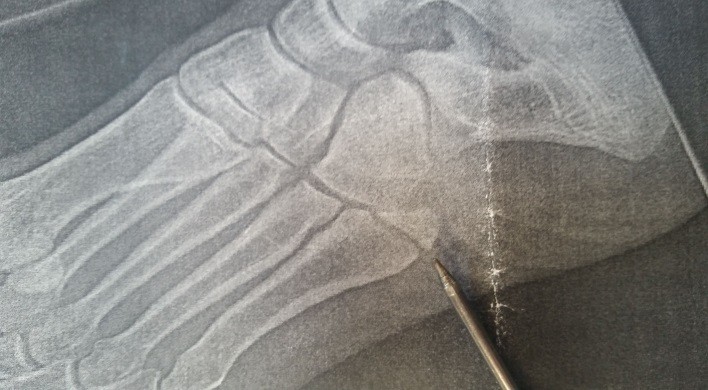

At around 14km in, I got pushed close to the verge by an on-coming car and turned over on my ankle, crushing the end off a bone in my foot (ouch!). Nightmare…. After a few minutes of hobbling/hopping and in a lot of pain, I managed to get running again. Thankfully, Mike had some pain killers which did the trick and helped me continue on with both feet.

7. I am dumb enough to be able to suffer a lot of pain….. Quote from the doctor – “yeah, you probably shouldn’t have run on that”…..